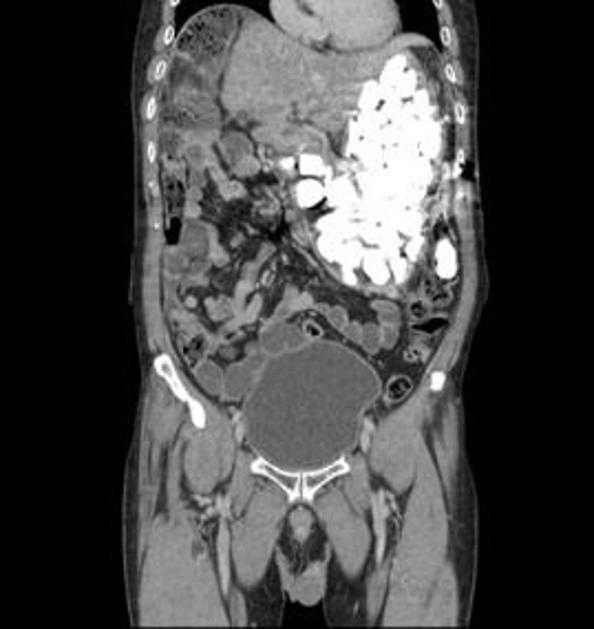

CT želodca American Journal of Medical Case Reports CT želodca